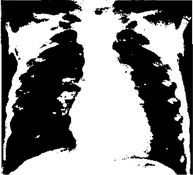

Рентгенологически определяется усиление сосудистого рисунка по артериальному типу, после 10-го дня жизни выявляется венозный застой. Отмечается прогрессирующее увеличение размеров сердца. Сосудистый пучок узкий в переднезадней проекции и расширен в боковой проекции. При параллельном расположении сосудов он расширен в переднезаднем отделе и оттесняет верхнюю полую вену вправо (рис. 21).

Рис. 21. Рентгенограмма органов грудной клетки с транспозицией крупных сосудов